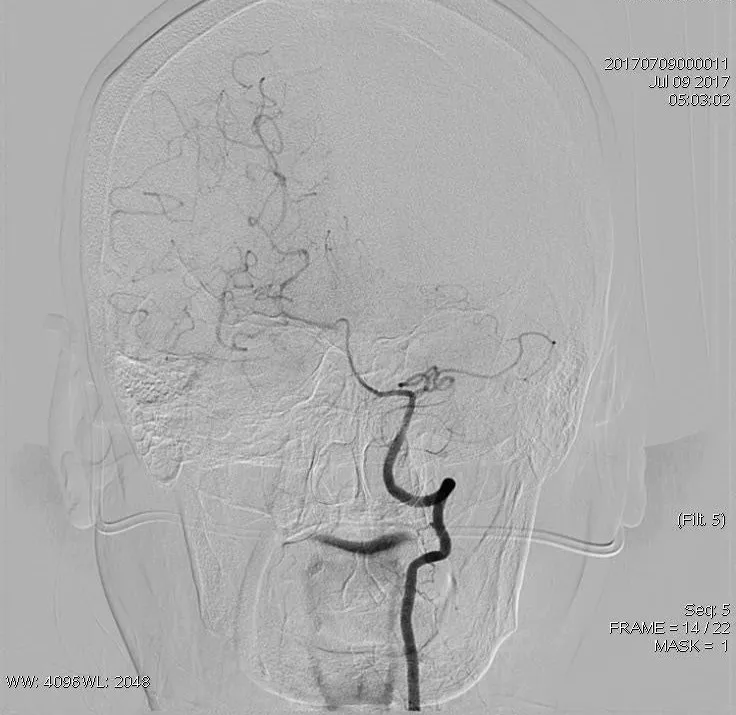

患者发病后1小时40分钟行穿刺。血管造影示,右侧颈总动脉(CCA)中部以远未见显影,术前mTICI分级:0级。

治疗开始时,因低压持续冒烟,发现患者大脑右侧的颈动脉窦部完全闭塞,因而首先解决近端病变。

8F指引导管联合6F Navien中间导管,冒烟证实,右侧CCA中段以远未见显影(A),造影证实,右侧ICA窦部以远未见显影(B)

再次造影发现,整个颈内动脉(ICA)C段通畅,但眼动脉段以远依然闭塞。

将导丝放置于病灶后,微导管放置到位,远端造影证实在血管腔内。置入6*30mm支架后,发现整个右侧MCA完全无显影。证实术前CT平扫高密度征的准确性,血栓负荷量比较大。

最后双支架联合抽吸拉通血栓。造影提示取栓后血管再通,TICI 3级。

造影提示取栓后血管再通,TICI 3级(A);抽吸联合取出的血栓(B)

术后造影评估发现,血流速度良好。

取栓后造影:TICI 3级